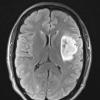

NEOPLASMS (GLIAL)

Astrocytoma, IDH-mutant, WHO Grade 2 (8)